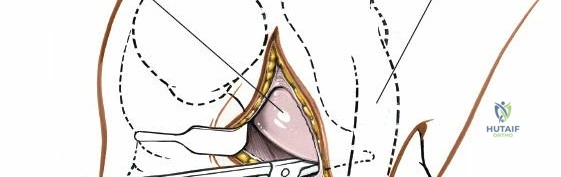

Exposure of the Meniscus:

- Retractors are carefully placed to expose the medial tibiofemoral compartment. Self-retaining retractors may be used, but care must be taken to protect the articular cartilage.

- To improve visualization, the knee is brought into hyperflexion (as per seed content, "beyond a right angle"). This maneuver, combined with external rotation of the tibia and a valgus stress applied to the knee, widens the medial compartment. This allows for improved access to the posterior horn of the medial meniscus.

Meniscectomy Technique (Partial):

- Inspection: Thoroughly inspect the medial meniscus to identify the tear pattern and assess its stability using a blunt probe.

- Resection: The goal is partial meniscectomy, removing only the unstable, symptomatic fragment. Total meniscectomy is strongly discouraged due to long-term sequelae.

- Specialized meniscal knives (e.g., banana knife, hook knife) are used to make precise cuts, detaching the torn fragment from the stable meniscal rim and meniscocapsular junction.

- Small rongeurs or basket forceps are then used to excise the torn portion.

- The remaining meniscal edge is carefully contoured and smoothed to prevent any residual tags from impinging or causing further irritation.

- "Removal of loose bodies" and "Removal of foreign bodies" are also performed at this stage if identified, utilizing the direct visualization offered by the open approach.